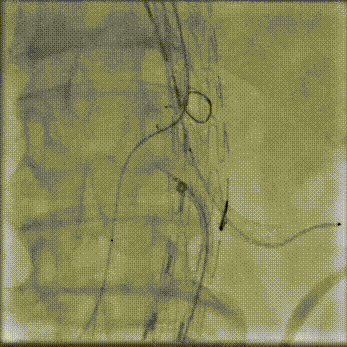

病史:68岁男性,胸腹主动脉夹层动脉瘤三年余,2021年接受B型夹层腔内修复术,术后恢复良好。近期复查发现腹主动脉夹层破口增大,假腔扩张明显。

手术方案:内脏区体外三开窗(CA、SMA、LRA),RRA原位开窗。

预三开窗+右肾原位开窗重建

Fustar+Futhrough原位穿刺破膜

预三开窗+肾动脉原位开窗重建